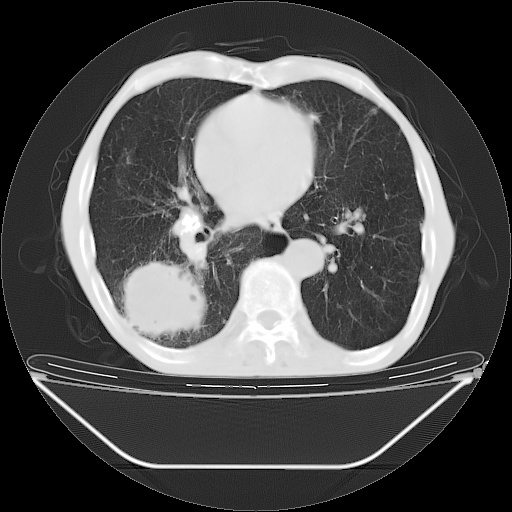

以下是引用随光逐影在2008-8-25 22:03:00的发言:[br]1)考虑右肺下叶周围性肺癌并肺内转移,腰椎附件转移。2)左上肺结核(结核球形成)。3)双肺肺气肿(多发肺大泡形成)。4)双肺门区及纵隔内多发淋巴结钙化。

以下是引用zsl6918在2008-8-25 21:55:00的发言:[br]符合右肺周围性肺癌并肺内转移,左肺结核球。双肺肺气肿。腰椎附件转移。

以下是引用qc80012345在2008-8-26 6:14:00的发言:[br]符合右肺周围性肺癌并肺内转移,左肺结核球。双肺肺气肿。腰椎附件转移。